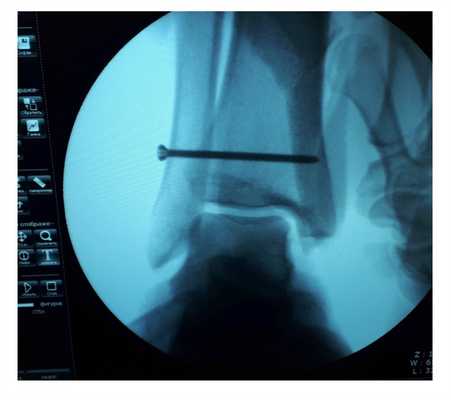

После восстановления латерального связочного комплекса по Брострому в модификации Голда и фиксации межберцового синдесмоза винтом производится оценка стабильности голеностопного сустава при помощи вальгус—стресс теста под контролем ЭОП.

Гипермобильность голеностопного сустава устранена, положение таранной кости остаётся неизменным несмотря на приложение вальгусной нагрузки.

Через 6 недель производится удаление позиционного винта. С этого момента разрешается полная осевая нагрузка.

На рентгенограммах видно что после удаления позиционного винта взаимоотношения большеберцовой и малоберцовой костей остаётся прежним, что свидетельствует в пользу того что лечение прошло успешно.